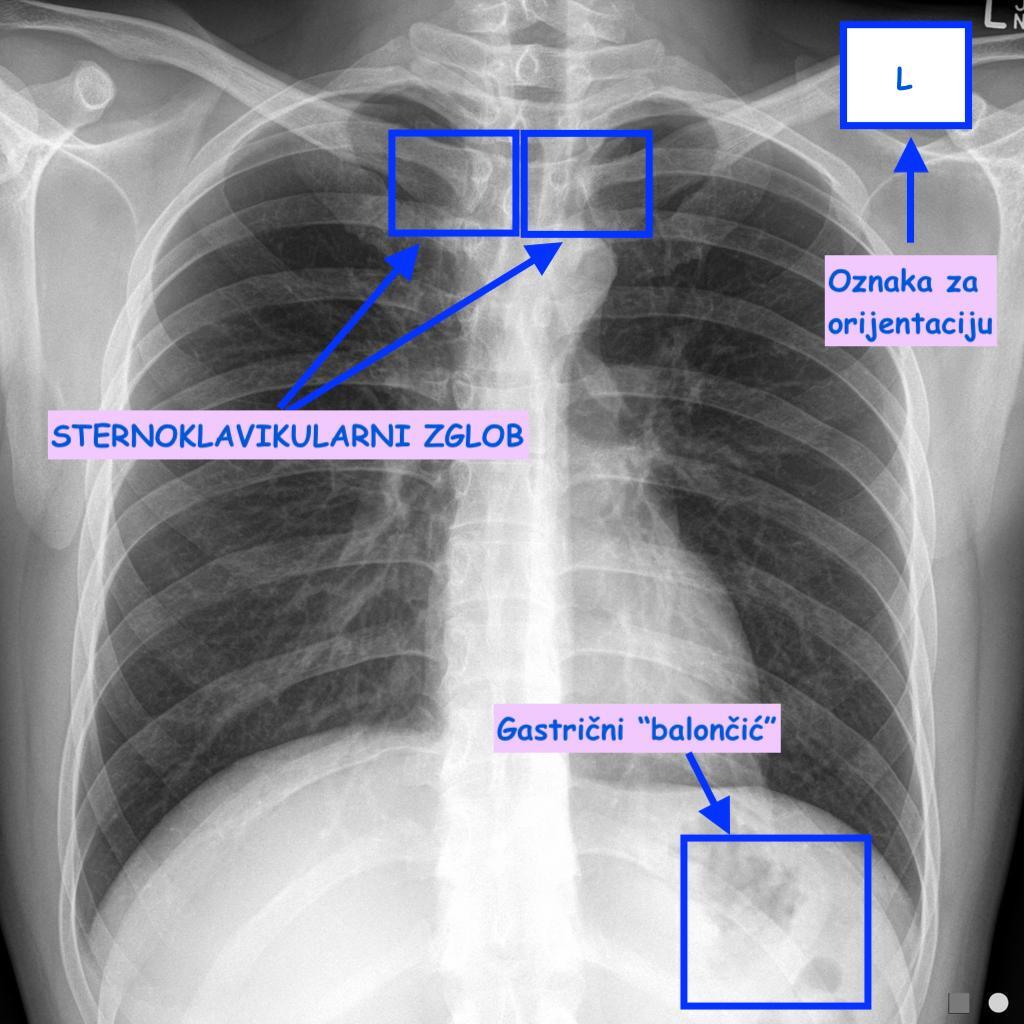

Analiza treba početi postavljanjem snimka na negatoskop (sunčeva svjetlost ili sijalica nisu dovoljni za analizu zbog neprilagođenog intenziteta), te snimak posmatrati tako da naša desna strana odgovara lijevoj strani bolesnika. Neophodno je provjeriti da li je snimak trajno označen stranom tj. desna (R) i lijeva (L), ali ne napisan, već nanesen prilikom fotografske obrade. Pored toga na snimku mora biti naznačeno ime i prezime bolesnika, te datum kada je načinjena snimka. Trebamo provjeriti projekciju i položaj bolesnika prilikom snimanja, te da li oznake strana snimka odgovaraju fiziološkoj poziciji anatomskih struktura( vrh srca, hemidijafragme, vazdušni mjehur u želucu. Ovo je posebno bitno kododređenih anatomskih varijacija ili patoloških stanja kao što je npr. dextrocardia. Rotacija bolesnika prilikom snimanja može dovesti do promjene položaja medijastinalnih organa i dovesti do pogrešnih dijagnoza. Da bi se utvrdila rotacija pacijenta posmatra se simetričnost sternoklavikularnih zglobova koji moraju biti u istoj visini i jednako udaljeni od srednje linije. Pored već navedenih vrši se provjera i drugih parametara kao što su :